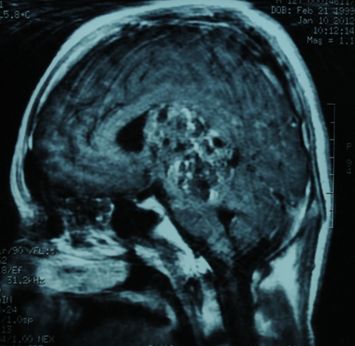

典型病例二:

手术前后